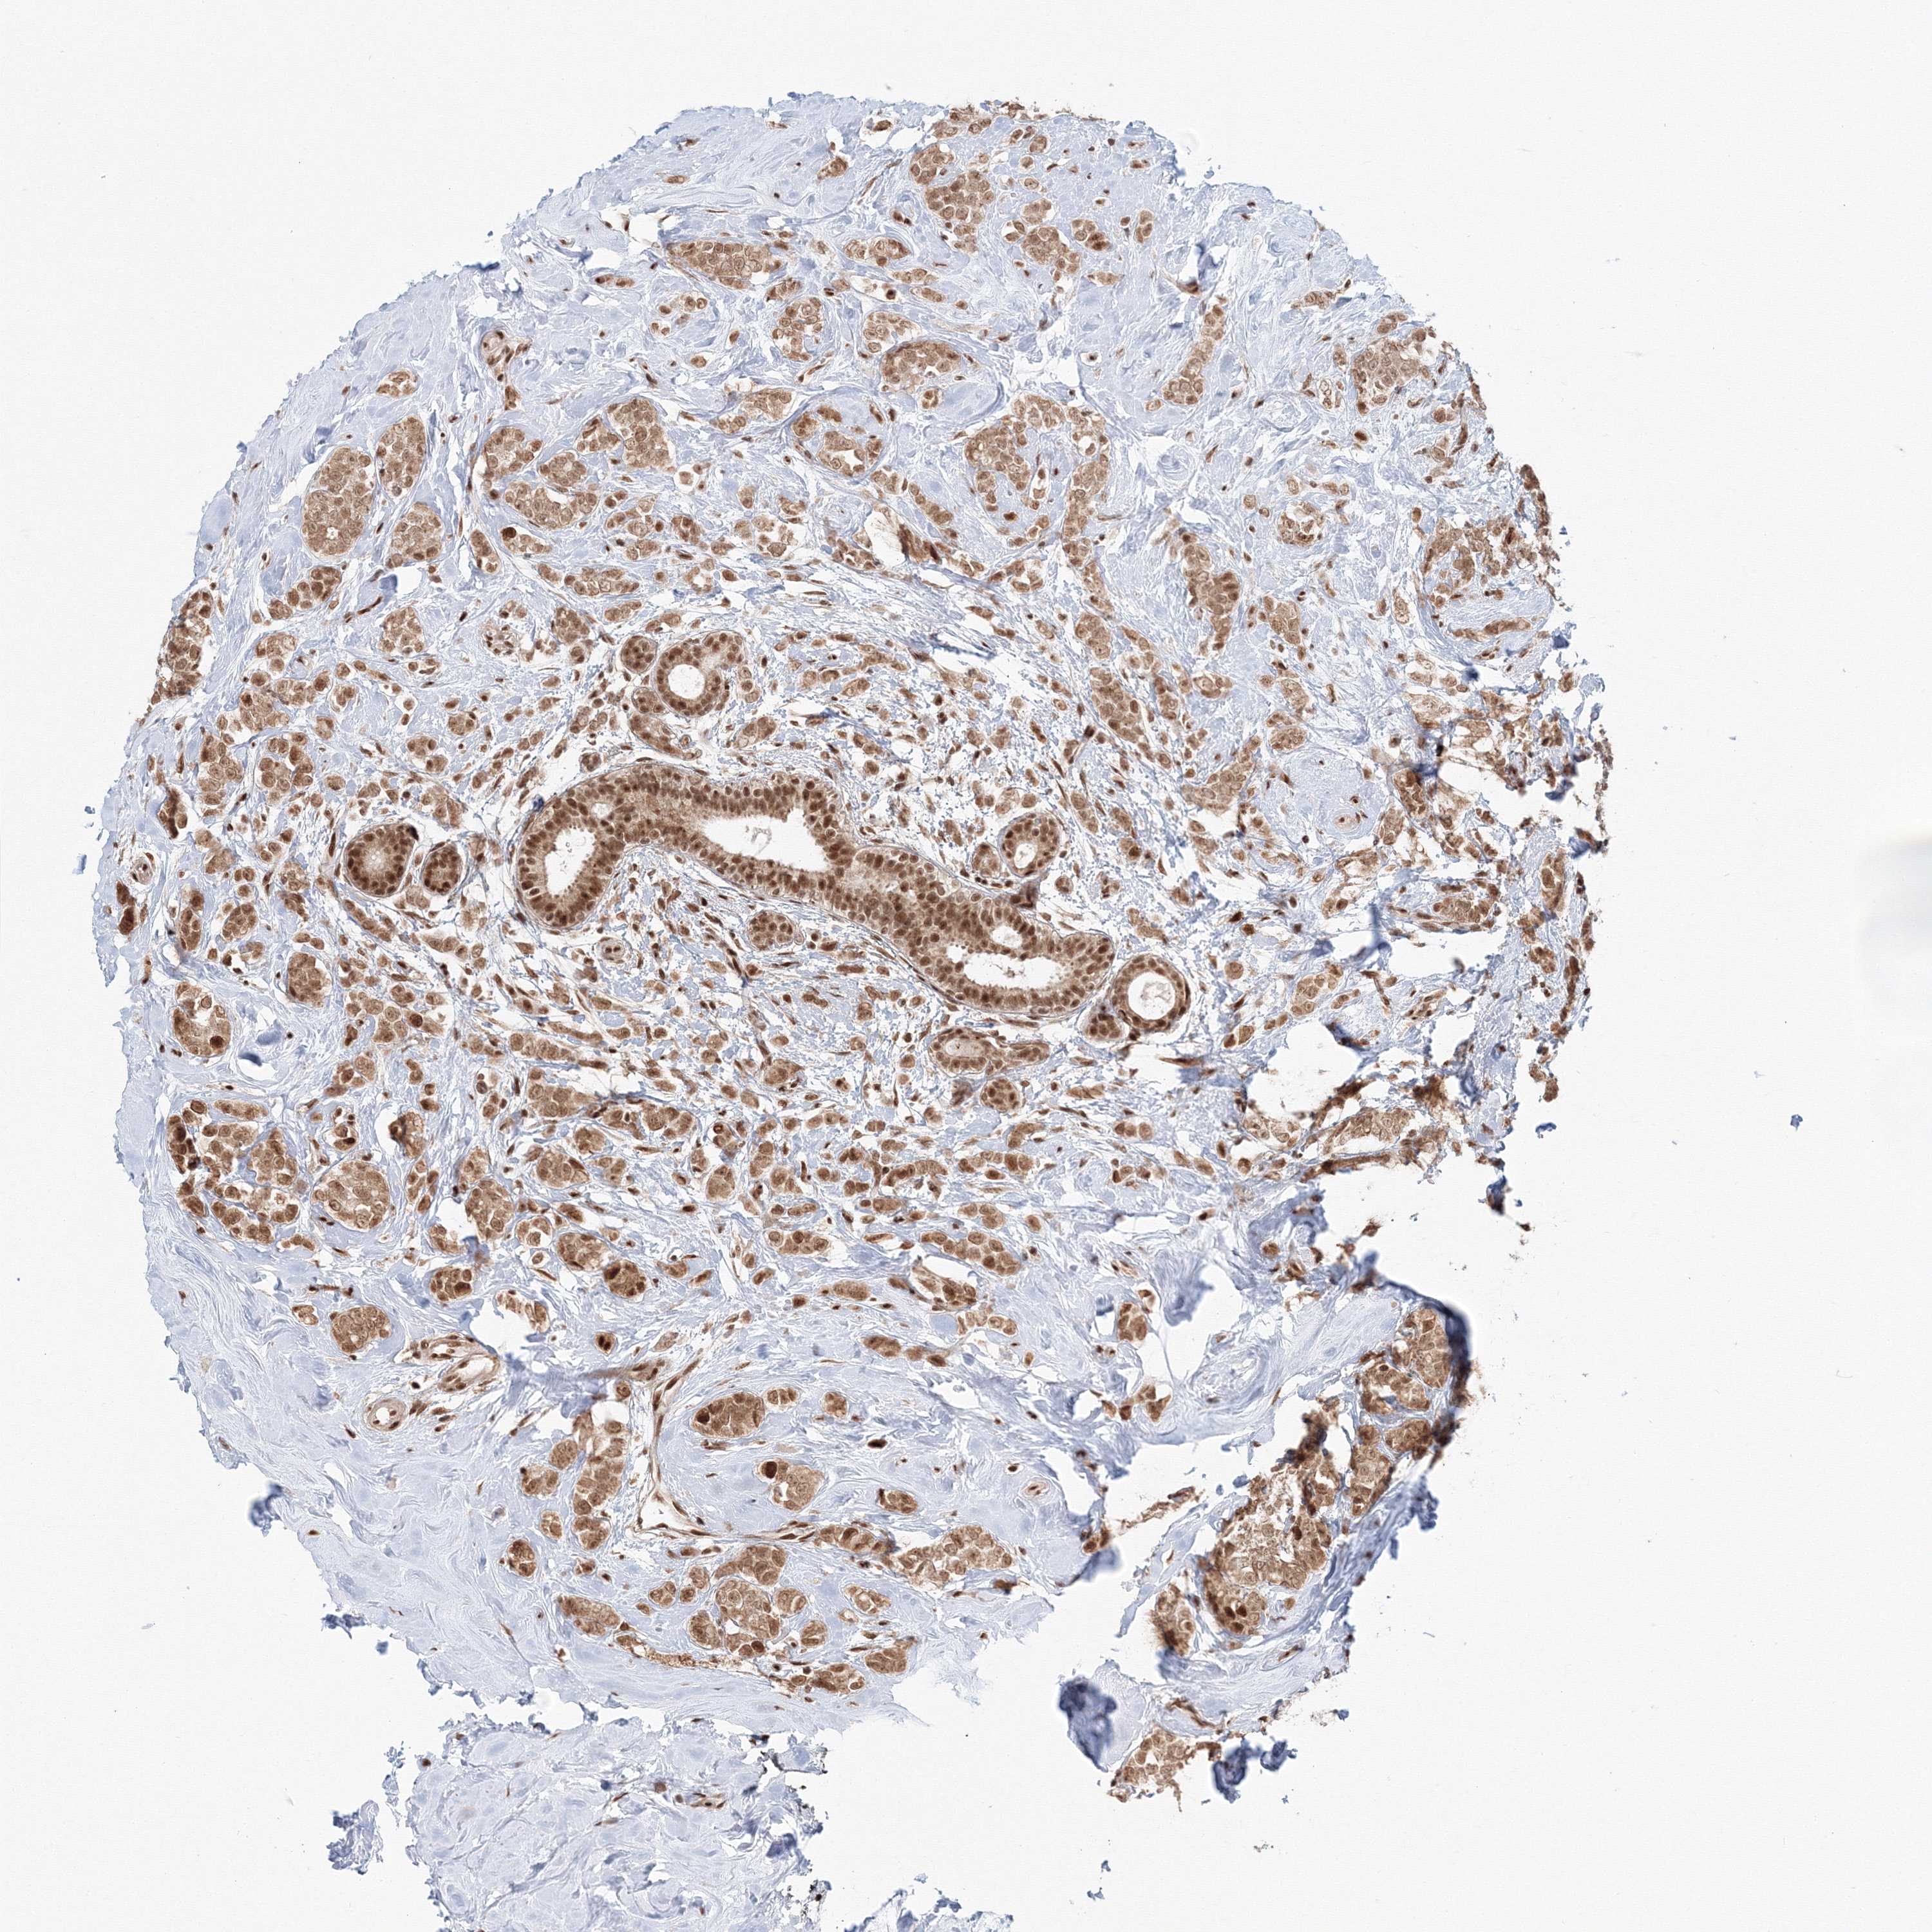

BRCA TCGA BRCA VALIDATION PROTEIN EXPRESSION